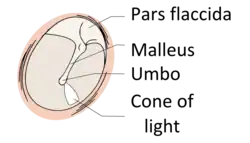

Hierbei sind die histologisch verschiedenen Trommelfellabschnitte mit zu berücksichtigen. Die kleine Pars flaccida oder auch Shrapnell’sche Membran besteht aus nur zwei Schichten; zum äußeren Gehörgang hin findet sich ein mehrschichtiges Plattenepithel, Stratum cutaneum, während zur Paukenhöhle hin ein einschichtiges Plattenepithel, Stratum mucosum ausgebildet ist. Zwischen den beiden unterschiedlichen Zellschichten liegt nur die Basallamina. Anders bei der größeren Pars tensa: Hier sind ebenfalls die beiden Zellschichten und die Basallamina ausgebildet, aber zusätzlich lassen sich noch zwei bindegewebige Faserschichten, Stratum fibrosum oder Lamina propria, unterscheiden. Eine dieser Faserschichten hat einen radiären Verlauf, Stratum radiatum, und die andere ist zirkulär angeordnet, Stratum circulare.

Der histologisch unterschiedliche Aufbau führt im Sinne einer Prädilektionsstelle zu einem begünstigten Auftreten etwa eines primären Cholesteatoms im Bereich der Pars flaccida, denn chronische Tubenbelüftungsstörungen können zu einer Retraktionstasche in der Pars flaccida führen. In einer solchen Retraktionstasche kommt es zu Epithelabschilferungen, die sich in der Folge in der Paukenhöhle ansammeln und über die Zeit und durch veränderte zelluläre Faktoren dann ein Cholesteatom ausbilden.

Die Diagnose wird mit Hilfe der Ohrmikroskopie gestellt. Der typische Befund ist ein Defekt in der Pars tensa oder Pars flaccida des Trommelfells mit Nachweis weißlich-gelber Schuppen oder Zellmassen in der Läsion. Nicht selten finden sich Polypen aus Granulationsgewebe. Untersucht man das Trommelfell durch die direkte Otoskopie, sieht man häufig eine Perforation des Trommelfells am oberen oder hinteren Rand.

Zumeist befindet sich das Cholesteatom am oberen, hinteren Teil der Paukenhöhle, so dass sich sein Detritus durch eine Perforation an der Pars flaccida des Trommelfells, seltener auch an der Pars tensa, dann aber am Rand nahe dem Faserring, Anulus fibrocartilagineus,[21] in den Gehörgang entleert.